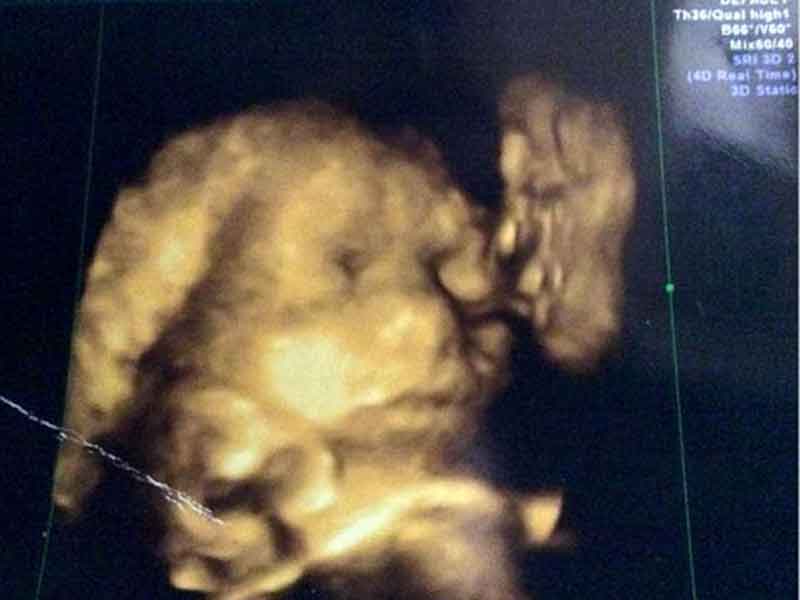

Mujer ve a su difunto abuelo besando a su bebé en ultrasonido 4D

Murió en 2007 y no tuvo la oportunidad de conocer a su bisnieta